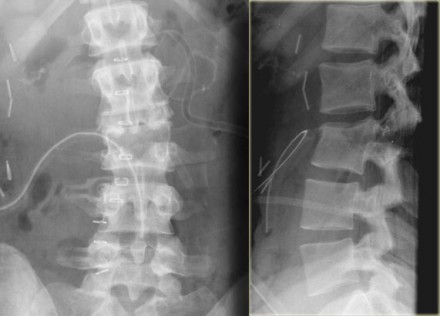

On the left another example of a Chance fracture.

Chance fracture (3)

On the left a Chance variant.

This is a pure ligamentous injury, which is analogous to bilateral

interfacet dislocation, which is also a pure ligamentous injury.

There is rupture of the interspinous ligament, dislocation of the facet joints and a horizontal rupture of the disc.

Pure ligamentous and combined osseous / ligamentous variants have an increased risk of instability compared to the osseus type.

Always look for a split of the posterior elements, disc widening or widening of the spinous processes and facets.